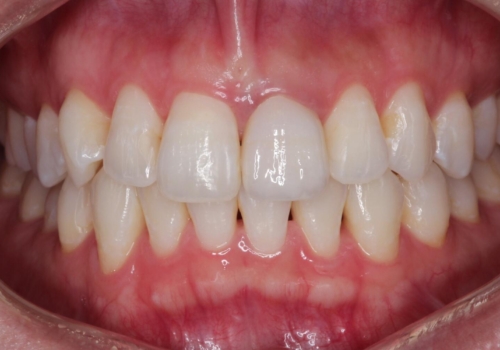

- 28.6万円(内訳:根管治療11万円、土台2.2万円、仮歯1.1万円、オールセラミック[スペシャル]14.3万円)費用は治療当時の料金となります

色や形など自然な仕上がりにご満足いただけました。